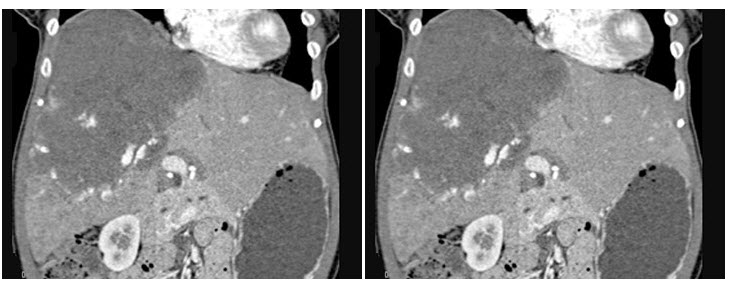

男,48岁,胃癌术后1年,未化疗,CT检查如图所示,最可能的诊断为()

A.肝癌

B.肝转移癌

C.肝血管瘤

D.肝脓肿

E.肝囊肿